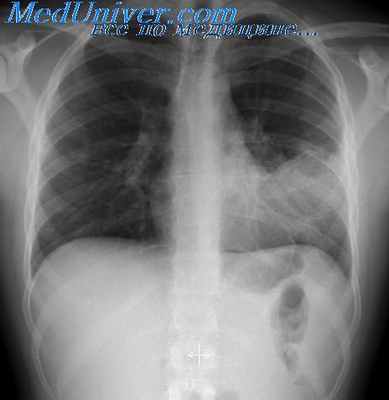

При работе на повышенных напряжениях, как и при рентгенографии на обычных напряжениях, необходимо использовать все известные способы борьбы с рассеянным рентгеновским излучением.

Количество рассеянных рентгеновых лучей уменьшается с уменьшением поля облучения, что достигается ограничением в поперечнике рабочего пучка рентгеновых лучей. С уменьшением поля облучения, в свою очередь, улучшается разрешающая способность рентгеновского изображения, т. е. уменьшается минимальный размер определяемой глазом детали. Для ограничения в поперечнике рабочего пучка рентгеновых лучей далеко еще недостаточно используются сменные диафрагмы или тубусы.

Для уменьшения количества рассеянных рентгеновых лучей следует применять, где это возможно, компрессию. При компрессии уменьшается толщина исследуемого объекта и, само собой разумеется, становится меньше центров образования рассеянного рентгеновского излучения. Для компрессии используются специальные компрессионные пояса, которые входят в комплект рентгенодиагностических аппаратов, но они недостаточно часто используются.

Количество рассеянного излучения уменьшается с увеличением расстояния между рентгеновской трубкой и пленкой. При увеличении этого расстояния и соответствующем диафрагмировании получается менее расходящийся в стороны рабочий пучок рентгеновых лучей. При увеличении расстояния между рентгеновской трубкой и пленкой необходимо уменьшать поле облучения до минимально возможных размеров. При этом не должна «срезаться» исследуемая область.

С этой целью в последних конструкциях рентгенодиагностических аппаратов предусмотрен пирамидальный тубус со световым центратором. С его помощью достигается возможность не только ограничить снимаемый участок для повышения качества рентгеновского изображения, но и исключается излишнее облучение тех частей тела человека, которые не подлежат рентгенографии.

Для уменьшения количества рассеянных рентгеновых лучей исследуемую деталь объекта следует максимально приближать к рентгеновской пленке. Это не относится к рентгенографии с непосредственным увеличением рентгеновского изображения. При рентгенографии с непосредственным увеличением изображения рассеянное изучение практически не достигает рентгеновской пленки.

Мешочки с песком, используемые для фиксации исследуемого объекта, надо располагать дальше от кассеты, так как песок является хорошей средой для образования рассеянного рентгеновского излучения.

При рентгенографии, производимой на столе без использования отсеивающей решетки, под кассету или конверт с пленкой следует подкладывать лист просвинцованной резины возможно больших размеров.

Для поглощения рассеянных рентгеновых лучей применяются отсеивающие рентгеновские решетки, которые поглощают эти лучи при выходе их из тела человека.

Освоение техники производства рентгеновских снимков при повышенных напряжениях на рентгеновской трубке является именно тем путем, который приближает нас к идеальному рентгеновскому снимку, т. е. такому снимку, на котором хорошо видны в деталях и костная, и мягкая ткани.